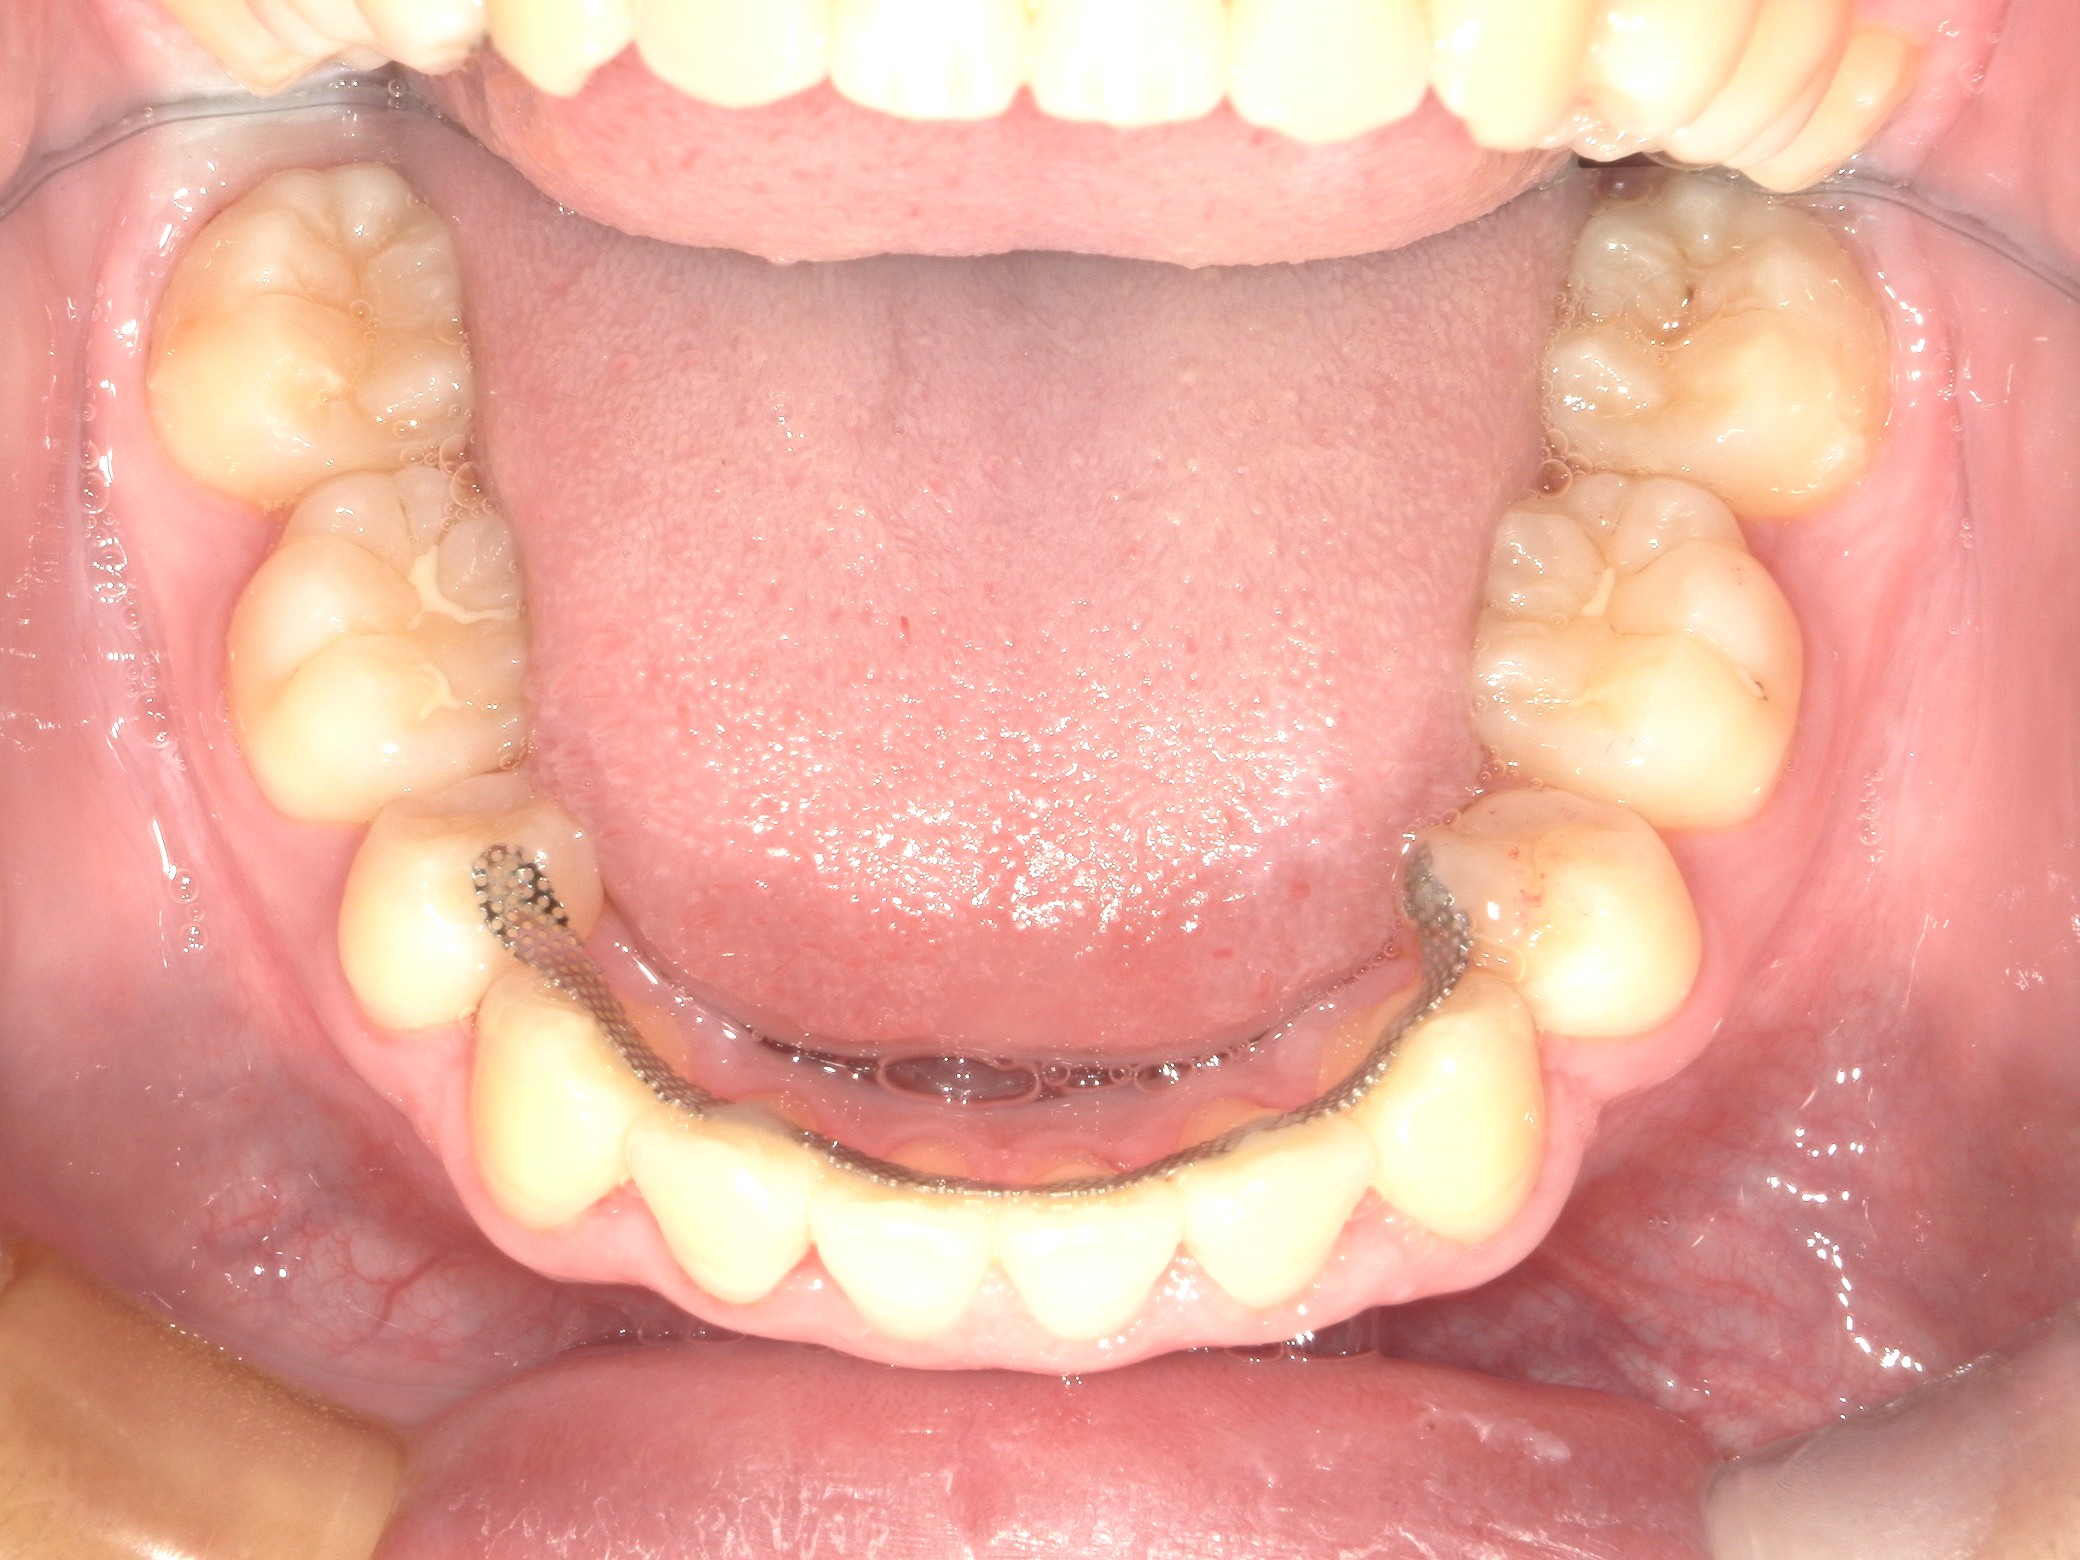

口内下

治療前

治療後